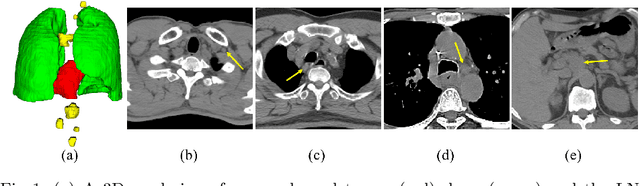

Abstract:Accurate organ at risk (OAR) segmentation is critical to reduce the radiotherapy post-treatment complications. Consensus guidelines recommend a set of more than 40 OARs in the head and neck (H&N) region, however, due to the predictable prohibitive labor-cost of this task, most institutions choose a substantially simplified protocol by delineating a smaller subset of OARs and neglecting the dose distributions associated with other OARs. In this work we propose a novel, automated and highly effective stratified OAR segmentation (SOARS) system using deep learning to precisely delineate a comprehensive set of 42 H&N OARs. SOARS stratifies 42 OARs into anchor, mid-level, and small & hard subcategories, with specifically derived neural network architectures for each category by neural architecture search (NAS) principles. We built SOARS models using 176 training patients in an internal institution and independently evaluated on 1327 external patients across six different institutions. It consistently outperformed other state-of-the-art methods by at least 3-5% in Dice score for each institutional evaluation (up to 36% relative error reduction in other metrics). More importantly, extensive multi-user studies evidently demonstrated that 98% of the SOARS predictions need only very minor or no revisions for direct clinical acceptance (saving 90% radiation oncologists workload), and their segmentation and dosimetric accuracy are within or smaller than the inter-user variation. These findings confirmed the strong clinical applicability of SOARS for the OAR delineation process in H&N cancer radiotherapy workflows, with improved efficiency, comprehensiveness, and quality.

Abstract:OAR segmentation is a critical step in radiotherapy of head and neck (H&N) cancer, where inconsistencies across radiation oncologists and prohibitive labor costs motivate automated approaches. However, leading methods using standard fully convolutional network workflows that are challenged when the number of OARs becomes large, e.g. > 40. For such scenarios, insights can be gained from the stratification approaches seen in manual clinical OAR delineation. This is the goal of our work, where we introduce stratified organ at risk segmentation (SOARS), an approach that stratifies OARs into anchor, mid-level, and small & hard (S&H) categories. SOARS stratifies across two dimensions. The first dimension is that distinct processing pipelines are used for each OAR category. In particular, inspired by clinical practices, anchor OARs are used to guide the mid-level and S&H categories. The second dimension is that distinct network architectures are used to manage the significant contrast, size, and anatomy variations between different OARs. We use differentiable neural architecture search (NAS), allowing the network to choose among 2D, 3D or Pseudo-3D convolutions. Extensive 4-fold cross-validation on 142 H&N cancer patients with 42 manually labeled OARs, the most comprehensive OAR dataset to date, demonstrates that both pipeline- and NAS-stratification significantly improves quantitative performance over the state-of-the-art (from 69.52% to 73.68% in absolute Dice scores). Thus, SOARS provides a powerful and principled means to manage the highly complex segmentation space of OARs.